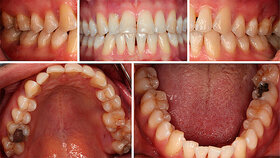

Die DDG rät allen Diabetespatienten zu gründlicher Mundhygiene und regelmäßiger Kontrolle durch einen Zahnarzt. Darüber hinaus sei es wichtig, auf die Blutzuckereinstellung zu achten, um das Risiko einer Parodontitiserkrankung zu senken.

"Ist der Blutzuckerspiegel des Diabetespatienten schlecht eingestellt, steigt das Risiko für Parodontitis stark an", erläutert DDG-Präsident Prof. Dr. med. Dirk Müller-Wieland. "Auch ist dann die Zahnfleisch-Behandlung komplizierter, der Krankheitsverlauf schwerer, ein Zahnverlust häufiger."

Umgekehrt verschlechtere eine Parodontitis wiederum die Blutzuckereinstellung – mit der Tiefe der Zahnfleischtaschen steige auch der Langzeit-Blutzuckerwert an. Untersuchungen zufolge ist die Sterblichkeit von parodontal erkrankten Diabetespatienten höher als bei Menschen mit gesundem Zahnfleisch. Grund sind Entzündungsprozesse, die sich unter anderem negativ auf das Herz auswirken.